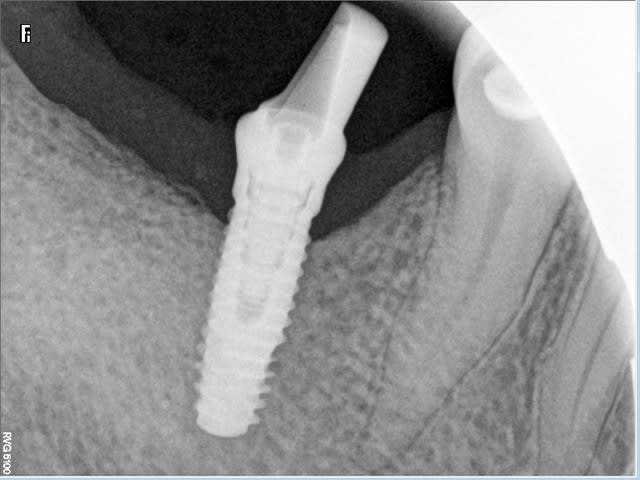

L'implant, un Biomet 3i 4,3mm a été posé en 46 par mon correspondant.

Avec le pilier droit, l'articulé serait en bout à bout avec 16 et distalé par rapport à la 45. Si je veux le point de contact, un grand porte à faux est necessaire.

Pour ce faire, il est possible d'utiliser un pilier angulé 15° qui mesialerait la couronne et retablirait un bon engrènement.

Le hic, selon moi, compte tenu du type morpho du patient est la transmission des forces de mastication avec risque de fracture de l'implant. Et ce d'autant plus qu'il y a une petite cratérisation et que par conséquent l'implant n'est pas entièrement enfoui.

le poseur aurait du penser à la prothèse avant de poser, et l'implant n'aurait il pas du être un peu plus profond?